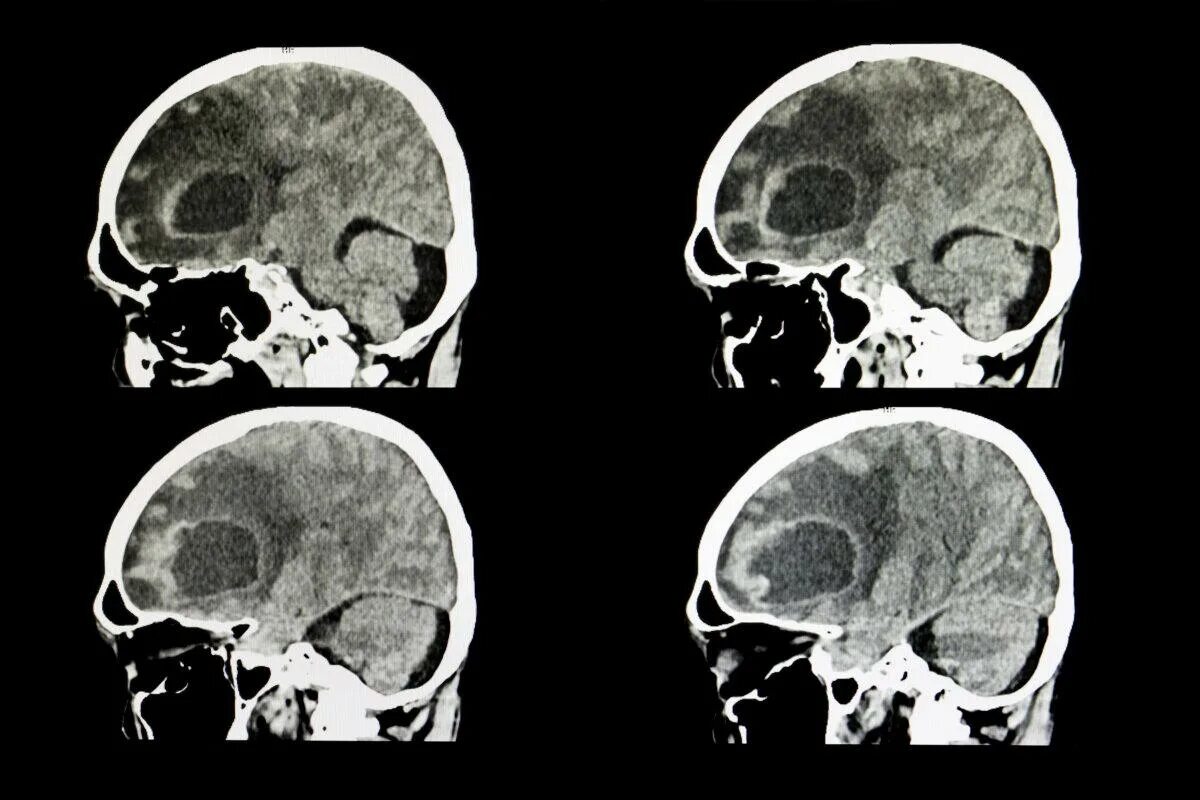

Ct search